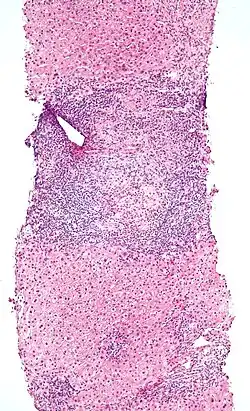

| Micrograph of PBC showing bile duct inflammation and injury, H&E stain | |

Intermediate-magnification micrograph of PBC showing bile duct inflammation and periductal granulomas, liver biopsy, H&E stain -

On microscopic examination of liver biopsy specimens, PBC is characterized by chronic, nonsuppurative inflammation, which surrounds and destroys interlobular and septal bile ducts. These histopathologic findings in primary biliary cholangitis include:[32]

- Inflammation of the bile ducts, characterized by intraepithelial lymphocytes

- Periductal epithelioid granulomas.

- Proliferation of bile ductules

- Fibrosis (scarring)